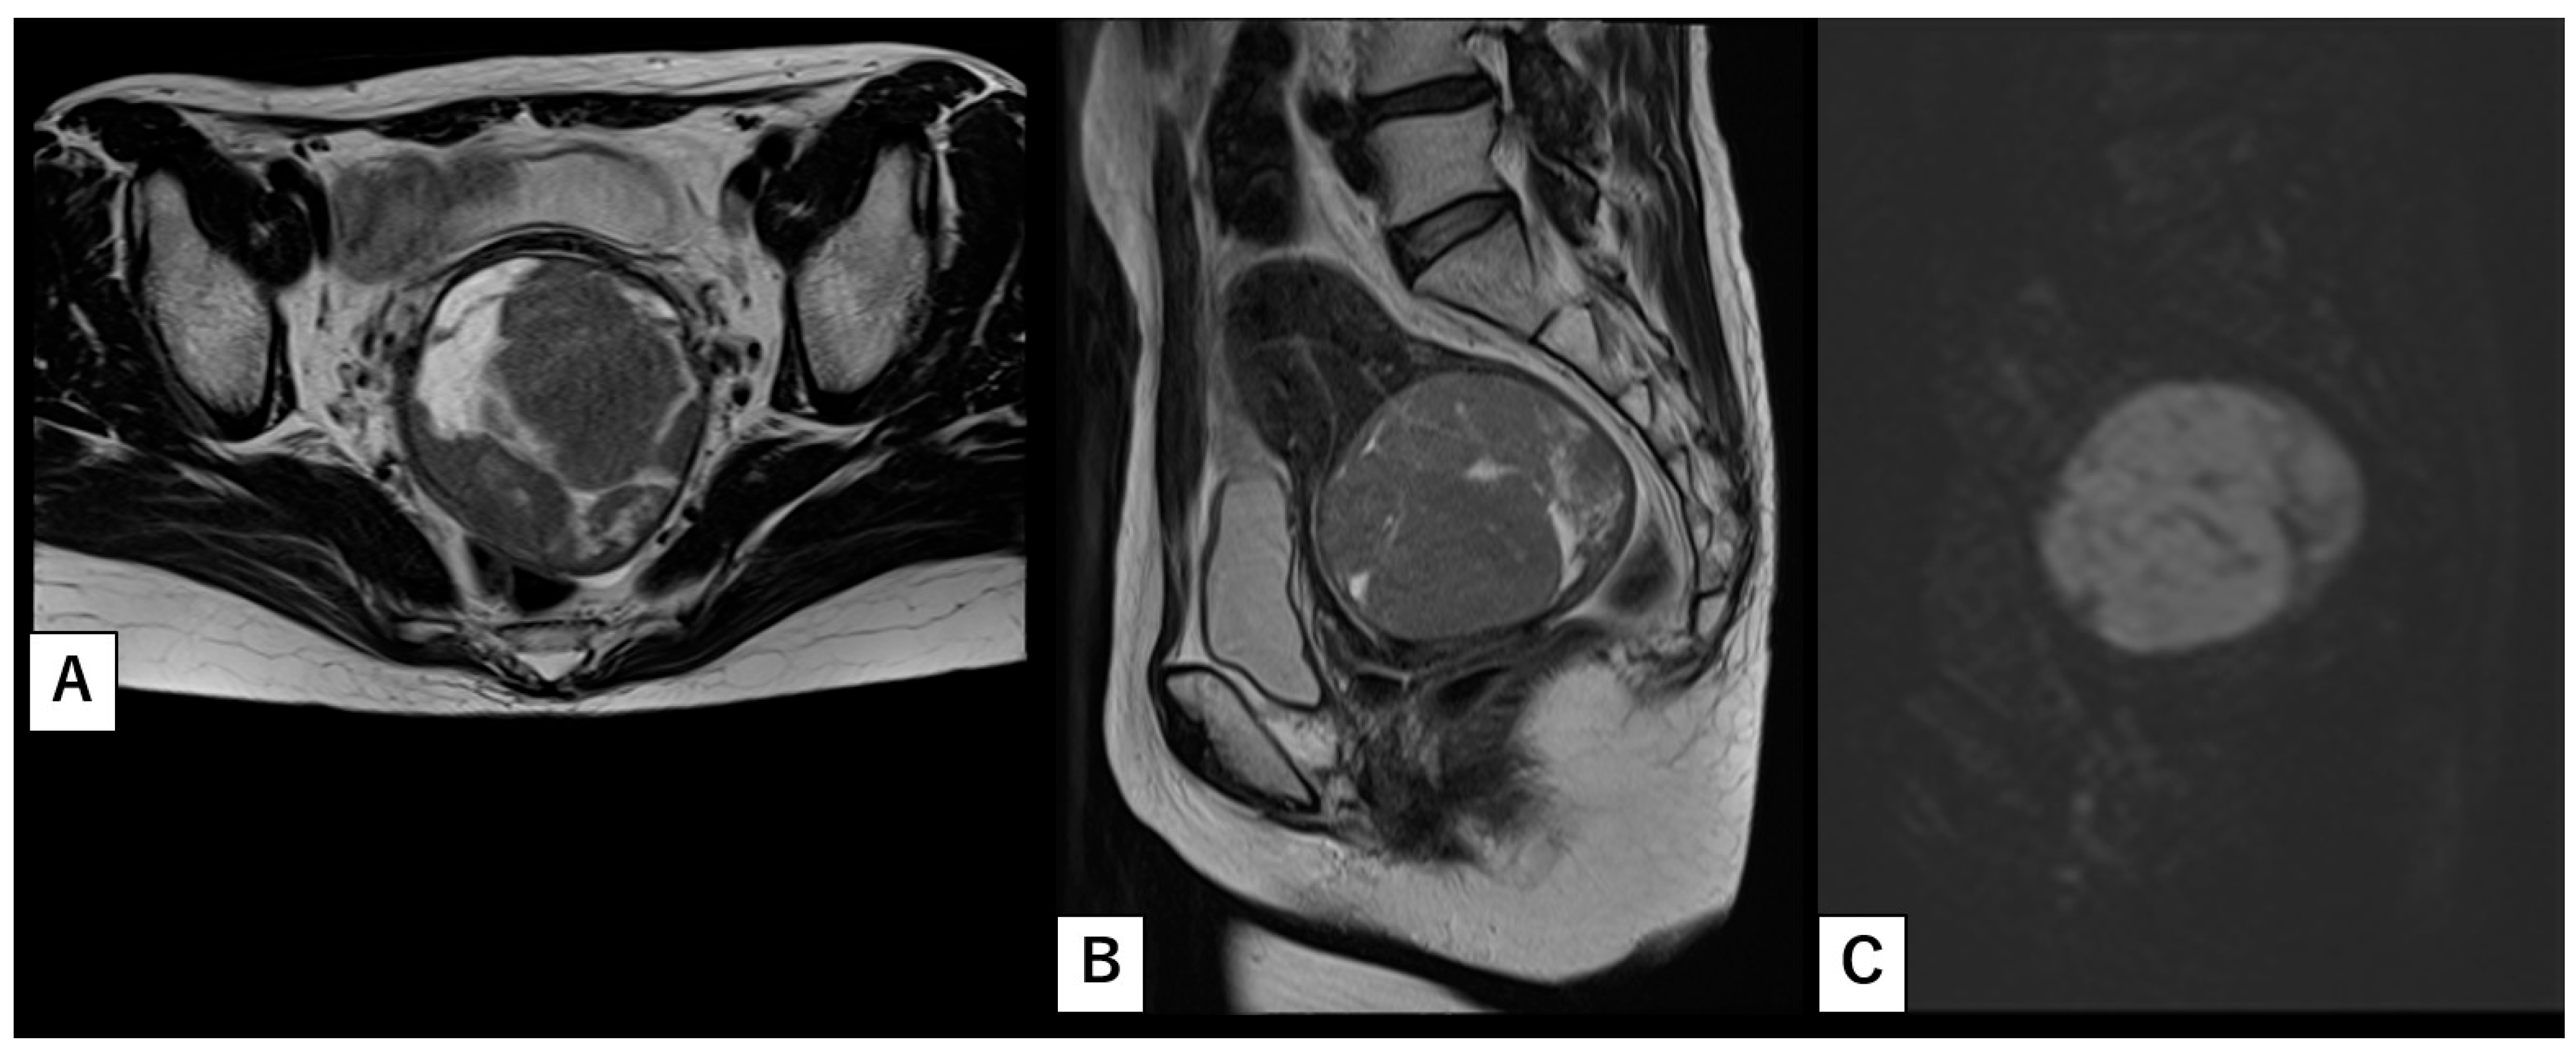

2. Case Report